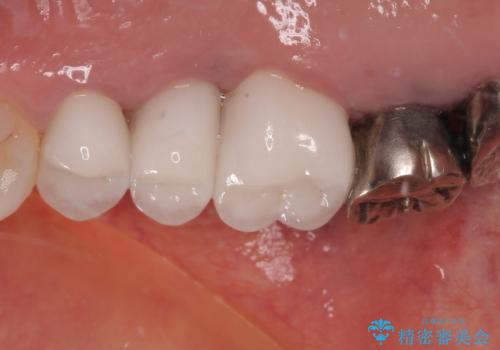

奥の銀歯の幅が大きかったこともあり、細長いクラウンの見た目は大きく改善することができました。

今後は他の銀歯の治療を進めていく計画です。